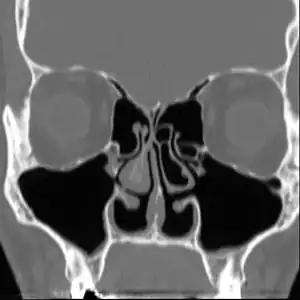

There are no objective physical examination findings that definitely diagnose ENS.[1] Generally, one or more turbinates may be reduced or absent when viewed in medical imaging or via endoscope with no sign of physical obstruction, the mucosa will be dry and pale, and there may be signs of secondary infection.[1]

No consensus criteria exist for the diagnosis of ENS; it is typically diagnosed by ruling out other conditions, with ENS remaining the likely diagnosis if the signs and symptoms are present.[1][2][6] A "cotton test" has been proposed, in which moist cotton is held where a turbinate should be, to see if it provides relief; while this has not been validated nor is it widely accepted, it may be useful to identify which people may benefit from surgery.[1][2][6]